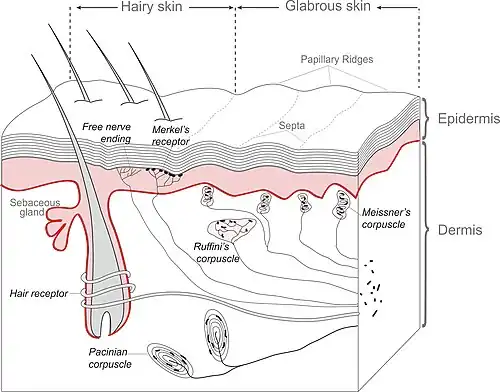

- Mechanical receptors

- Pressure:

- Fast adaptation (Meissner’s corpuscle, Pacinian corpuscle) ? movement

- Slow adaptation (Merkel disks, Ruffini endings) ? shape Comment: these signals are transferred fast

- Muscle spindles

- Golgi organs: in the tendons

- Joint-receptors